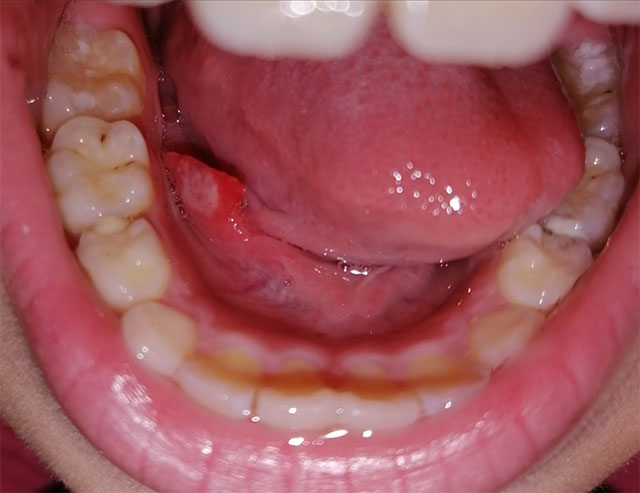

心急!請問這是口腔癌症狀嗎?!

只是一般的口水腺發炎。